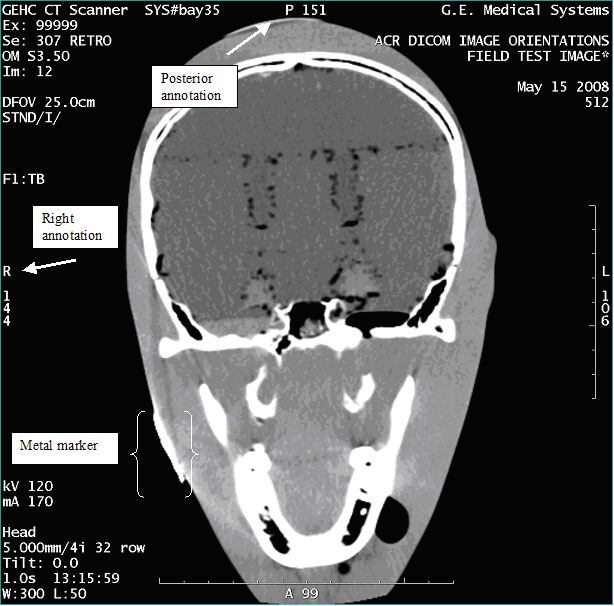

- With the support of the site personnel, examine the images sent

to the Review Station (i.e., 12 series, each with 1 image) and compare

their orientation to the images in this document.

- Each image contains a metal marker on the phantom's right cheek.

- Each image in this document contains a description of the expected

orientation of the metal marker (i.e. to prove Left and Right) as

well as the Posterior and Anterior orientation description.note:

The sample images included in this document use “R”, “L”, “P”, and “A” for “Right”, “Left”, “Posterior” and “Anterior” orientation. The Hospital Review Station may use a different style of annotation. The style used is not relevant to this procedure.

Figure 3. Exam 99999, Series 307